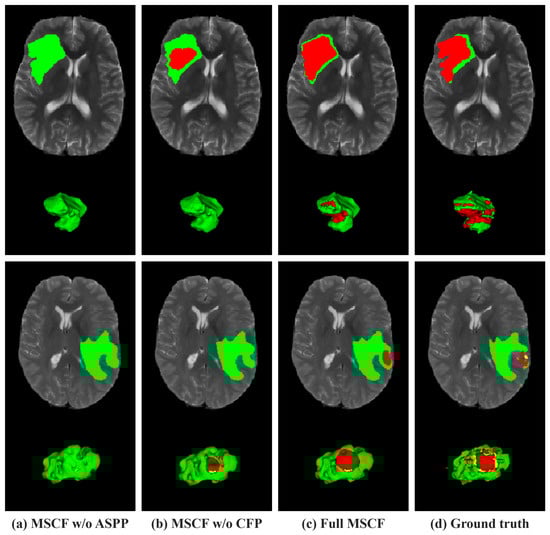

Figure 8 presents visualization results of the ablation study for the configuration modules on the BraTS 2020 dataset. From left to right, each column represents the base model, the model incorporating the TACR module, the model introducing both the TACR and MSCF modules, the model introducing both the TACR and 3D ARA modules, the model with all the modules integrated, and ground truth. In the visualization results, the performance in the ED region, marked in green, was inaccurately predicted across all models, excluding the model incorporating all modules. Specifically, in the first row, there was a failure to predict the ED region located on the right side, which aligned with the ground truth. Conversely, in the second row, normal tissue was erroneously identified as the ED region.

Figure 8.

Visual comparison of tumor segmentation outputs from different configurations of the proposed model on the BraTS 2020 dataset. The colors indicate regions of tumors. Red: NCR/NET; yellow: ET; green: ED.